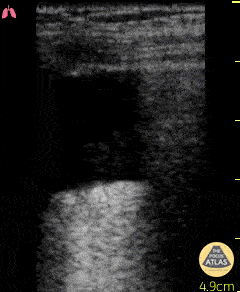

Question 4: You are paged by the radiology resident because a patient has a pneumothorax. They are concerned about the following chest X-ray:

You go to examine the patient and they are eating dinner and watching television. You lie the patient flat on the bed and perform thoracic ultrasonography on the right chest. Throughout the chest you see the following pattern:

Questions:

- What do you think is going on?

- What information would you seek next?

- How would you manage this situation?